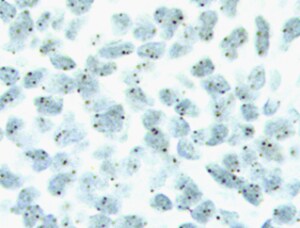

Dagan Wells of Oxford University and his colleagues recently used the Ion PGM™ System to identify chromosomal abnormalities in archived samples in less than 15 hours, their NGS tests were shown to be highly sensitive and specific (and compared favorably to microarray techniques). The researchers performed low-pass whole-genome sequencing on a 61 retrospective single-cell samples—six were derived from cell lines, and 38 from embryonic samples, including 32 blastocysts.

The blastocyst samples were multiplexed on a single Ion 316™ Chip. Comparisons to aCGH results showed a chromosome concordance rate of 99.7 percent. In addition, the study revealed an association mitochondrial DNA (mtDNA) and aneuploidy where embryos that exhibited elevated amounts of mtDNA appeared to be at a greater risk of chromosomal abnormalities. These results suggest indicating areas of fertile future research.